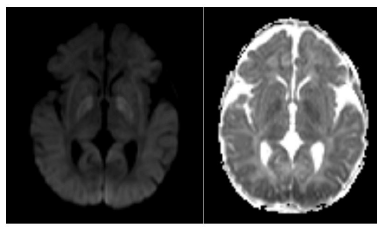

After weaning from sedation and analgesia, she maintained an altered mental status with spontaneous eye opening but no fixation or gaze following, poorly reactive isochoric pupils, and symmetrical but small amplitude mobilization of the four limbs. Transfontanellar ultrasound showed diffuse cerebral edema, and brain magnetic resonance imaging revealed severe hypoxic-ischemic encephalopathy consistent with the clinical findings (Figure 2). The electroencephalogram showed diffuse slowing of brain activity without epileptic activity.